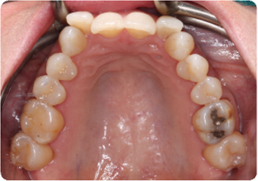

Each case shows the front view and an arch or side view, before and after BioLign Method-guided treatment.

All cases treated within 6–12 months.

High canine brought into the arch without extraction